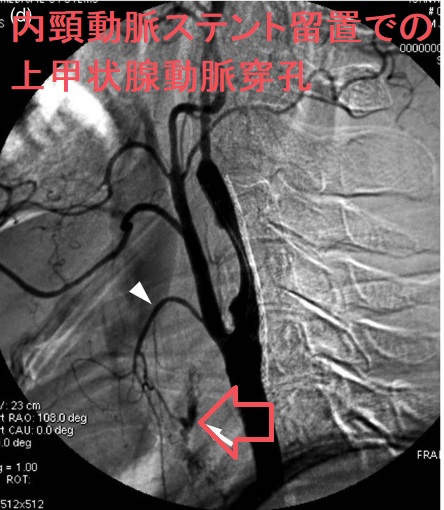

甲状腺機能低下症/潜在性甲状腺機能低下症/橋本病、糖尿病などでは動脈硬化が進み、頚動脈プラークにできた血栓が脳へ流れて脳梗塞。最悪、頚動脈自体の閉塞も。血管エコーでプラークを探す。動脈硬化血管は硬くもろく、大動脈では血圧に負けて大動脈瘤に。頸動脈閉塞度70%以上でカテーテル手術、ステント留置。時間が経つとステント上に新たなプラーク形成。内頸動脈ステント留置時、ガイドワイヤーで外頸動脈枝の上甲状腺動脈穿孔おこした報告あり。コレステロール/脂質塞栓が、網膜動脈を完全/不完全閉塞すると黄色斑(ホレンホースト斑)が生じる。

カテーテル手術、ステント留置

頸動脈ステントを留置した患者の甲状腺 超音波(エコー)画像;写真の頸動脈ステントを留置した患者は、甲状腺機能低下症/橋本病により動脈硬化が進行していました。(甲状腺と動脈硬化)

脳卒中治療ガイドライン 2021〔改訂2025〕では、軽度~中等度の頸動脈狭窄に頸動脈ステント留置や手術によるプラーク除去(頸動脈内膜剥離術)を行わないよう勧めています。

高度狭窄か脳梗塞を伴う中等度以上狭窄に対し、頸動脈ステント留置よりも手術によるプラーク除去(頸動脈内膜剥離術:CEA)を推奨しています。手術不能例には頸動脈ステント留置(CAS)。